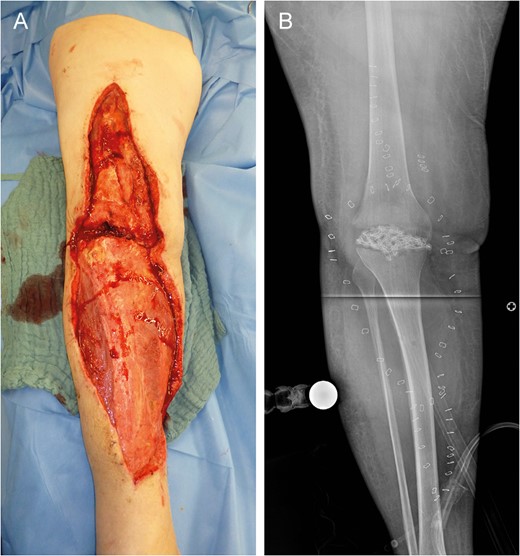

Near-total flap loss on Day 22. Note the livid discoloration of the monitor island (asterisk) indicating severe tissue hypoxemia (A). Above knee amputation site (B).